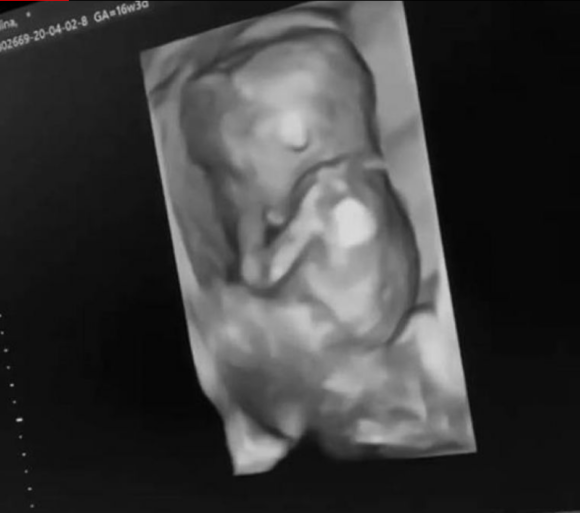

Fermecătoarea Alina Ceuşan va deveni mamă pentru prima dată anul acesta. Ea a postat în mediul virtual pentru prima dată imagini în care se poate observa foarte clar burtica de gravidă. Aşa cum era de aşteptat, mesajele din partea admiratorilor şi aprecierile dar și comentariile nu au întârziat să apară. Alina Ceuşan şi soţul ei, Raul Tişa, vor deveni părinţi pentru prima dată anul acesta în toamnă.